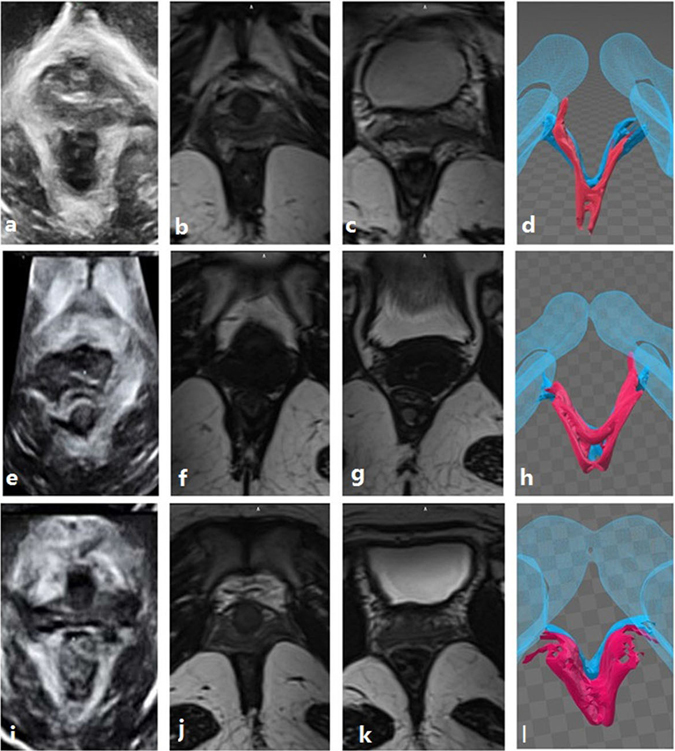

Figure 5.

The ultrasound images, MRIs and three-dimensional models of the three cases are shown. (a–l) Represent the same cases, respectively. Images in the first column are ultrasound images, images in the second column are MRIs used to observe the puborectalis, and images in the third column are MRIs used to observe the iliococcygeus and 3D model which show a tomographic overview of the puborectalis and iliococcygeus. Images in the first line are the left puborectalis avulsion with left iliococcygeus avulsion. The images in the second line are the right puborectalis avulsion without iliococcygeus damage. The images in the third line are the bilateral puborectalis avulsion with left iliococcygeus avulsion, including the left internal obturator muscle injury.

Comparison between MRI and ultrasound results

Puborectalis avulsions were on the left (n = 3), on the right (n = 4) or bilateral (n = 4) on ultrasound images. Similarly, the MRI results demonstrated puborectalis avulsions occurred on the left (n = 4), on the right (n = 4) or bilaterally (n = 3). MRI and ultrasound have good consistency in diagnosing puborectalis avulsion (concordance rate = 90.9%, the kappa coefficient = 0.864) (Table 3) (Fig. 5).